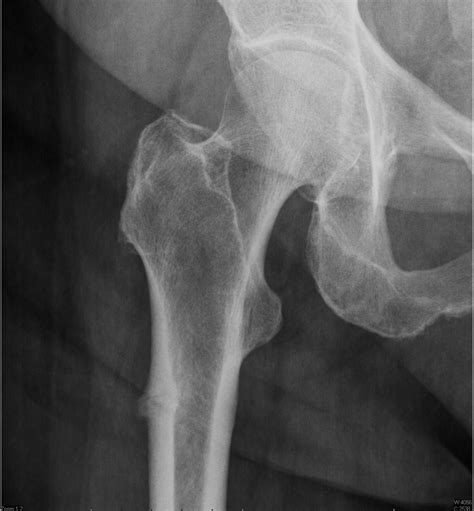

Fracture | Types, Causes & Symptoms | Britannica